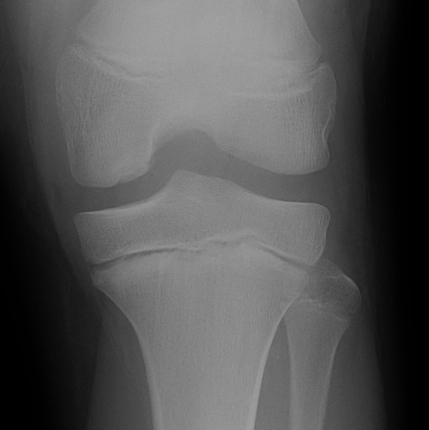

Xray

Intercondylar view / notch / tunnel view imperative

- most commonly seen in this view

- can miss the lesion unless have flexed knee view 30-50o

Xray classification

Stage 1: Normal / abnormal MRI

Stage 2: Lucent area of subchondral bone, can have surrounding sclerosis

Stage 3: Partial loosening

Stage 4: Completely detached / loose body

Type 2 Type 3 Type 3